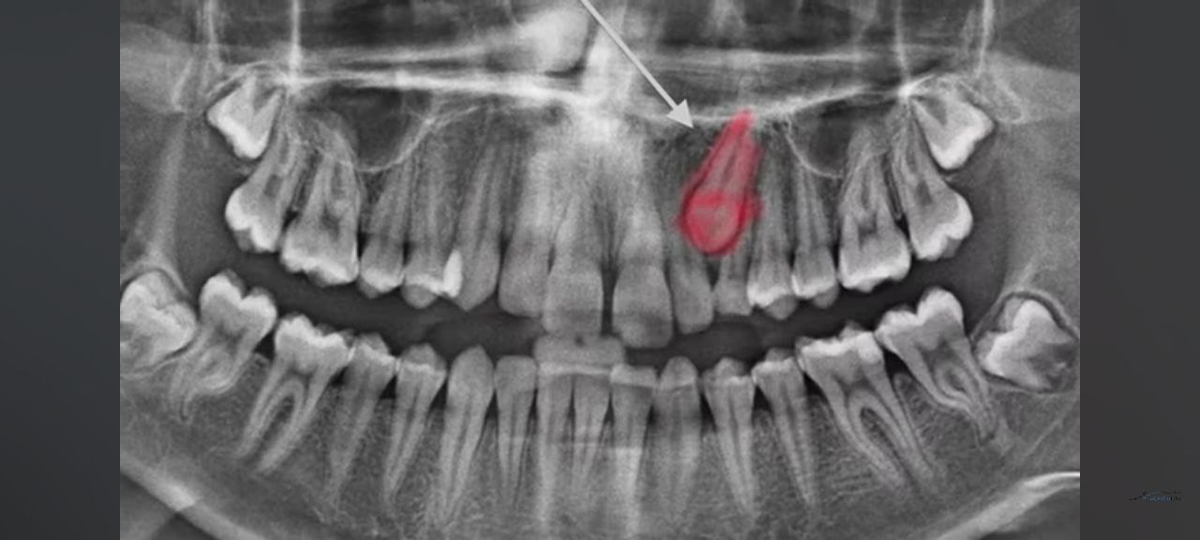

Согласно статистике до 18% людей страдают от того, что у них не прорезывается верхний клык. Он застревает около полости носа и не может прорезаться в полость рта. Но за рубежом эта статистика куда более благоприятна. Частота ретенции клыков у них достигает всего лишь 3-4%. Кстати, а поделитесь, в каком возрасте вы решили поставить себе брекеты и устранить проблемы с зубами? Клык играет ключевую роль в зубочелюстной системе, располагаясь на границе между передним и боковым отделами. Он служит защитой для всей системы зубов от разрушений. Отсутствие клыка в полости рта может привести к серьезным проблемам с зубами, включая их стирание, скалывание, разрушение и потерю с возрастом. Поэтому крайне важно извлекать клык при необходимости. Часто процесс его извлечения требует нескольких вмешательств, в ходе которых хирургически создаются доступы. После этого клык фиксируется к брекет-системе, установленной на верхних и нижних зубах, и постепенно выводится в полость рта. Как только клык успешно

Согласно статистике до 18% людей страдают от того, что у них не прорезывается верхний клык. Он застревает около полости носа и не может прорезаться в полость рта. Но за рубежом эта статистика куда более благоприятна. Частота ретенции клыков у них достигает всего лишь 3-4%.

Клык играет ключевую роль в зубочелюстной системе, располагаясь на границе между передним и боковым отделами. Он служит защитой для всей системы зубов от разрушений. Отсутствие клыка в полости рта может привести к серьезным проблемам с зубами, включая их стирание, скалывание, разрушение и потерю с возрастом. Поэтому крайне важно извлекать клык при необходимости.

Часто процесс его извлечения требует нескольких вмешательств, в ходе которых хирургически создаются доступы. После этого клык фиксируется к брекет-системе, установленной на верхних и нижних зубах, и постепенно выводится в полость рта. Как только клык успешно установлен, он начинает выполнять свои функции. Для достижения оптимальных результатов требуется около 3,5 лет ортодонтического лечения, дополненного хирургическими процедурами по извлечению клыка.